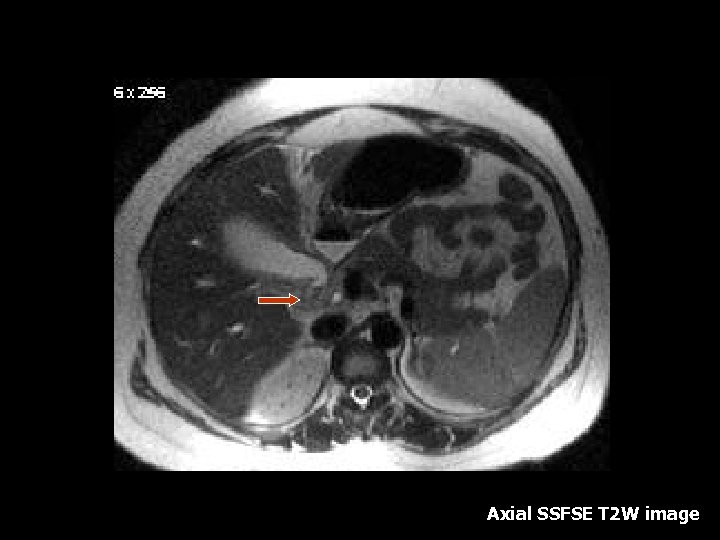

Dilated intra- and extrahepatic biliary dilatationwith a hypointense stone in the distal common bile duct Thick slice SSFSE coronal image

T 2 w FSE axial image with fa Hypointense stone in the distal common bile duct suppression

Choledocholithiasis • Heavily T 2 weighted images can show filling defects within the CBD and secondary signs such as CBD and intrahepatic biliary dilatation(2). • Treatment: cholecystectomy • MRCP images – heavily T 2 weighted images in a 3 D display can demonstrate filling defects within the CBD as well as secondary signs such as biliary system dilatation.